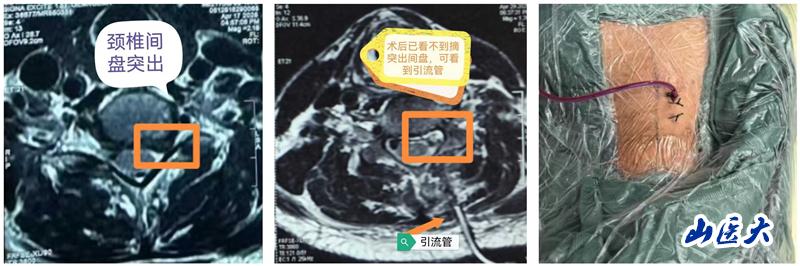

近日,我校第二醫院骨科脊柱二病區王少偉教授團隊成功為一例神經根型頸椎病患者實施了單側雙通道內鏡下的頸椎Keyhole(俗稱“鑰匙孔”)微創手術。手術全程順利,術中精準解除患者神經壓迫,術后患者左上肢疼痛即刻解除,術后第二天便可下床正常行走。

頸椎Keyhole微創手術是指在椎板上開設一個如鑰匙孔般精細的通道,通過脊柱內鏡技術完成病灶清除與神經減壓。該術式不僅最大程度地保留正常解剖結構,還能有效緩解神經根壓迫,為頸椎疾病患者帶來更加舒適的治療體驗和更快的康復進程。近年來,隨著脊柱內鏡技術的迅猛發展,單側雙通道內鏡技術在腰椎疾病的治療中得到了廣泛應用,如今,這項先進技術正逐步延伸至頸椎領域,開啟了頸椎治療的全新篇章。作為一項突破性的微創治療手段,Keyhole入路為神經根型頸椎病的手術治療提供了更安全、更精準、更高效的解決方案。